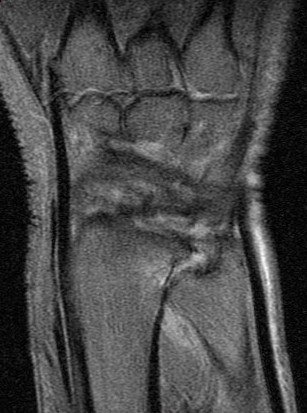

Ulnar impingement syndrome